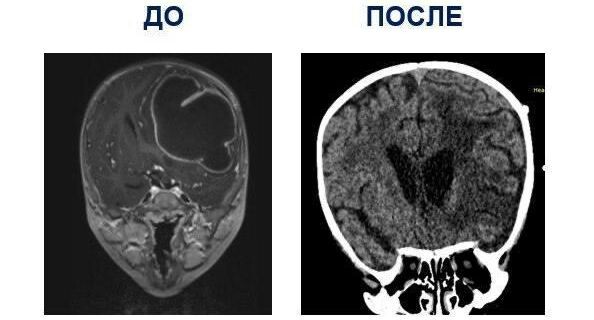

Нейрохирурги медцентра Рошаля спасли ребенка с крупным внутричерепным абсцессом

«У ребенка было очень опасное состояние — внутричерепной абсцесс большого объема — более 80 миллилитров. Точную причину его появления назвать сложно, с большей вероятностью — это неправильное домашнее лечение отита. Без срочной операции это могло бы привести к тяжелым последствиям: повреждению мозга, пожизненному параличу, эпилепсии или даже летальному исходу», — пояснил заведующий нейрохирургическим отделением центра Аслан Текоев.

Врачи определили местоположение гнойника, вскрыли его, удалили скопившуюся субстанцию и установили дренажную трубку.

После успешного вмешательства мальчик чувствует себя хорошо. Его уже выписали.